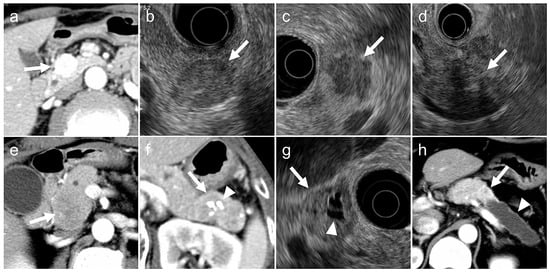

- (a)

- tumor margin contour on EUS (regular or irregular),

- (b)

- internal echogenicity on EUS (homogeneous or heterogeneous),

- (c)

- arterial phase enhancement pattern on contrast-enhanced CT (presence or absence of early enhancement),

- (d)

- presence of calcifications on CT or EUS (identified as hyperechoic structures or high-attenuation areas),

- (e)

- presence of cystic degeneration on CT or EUS (non-enhancing anechoic areas),

- (f)

- main pancreatic duct (MPD) dilation (MPD diameter ≥3 mm on CT or EUS).

- Irregular tumor margins: tumors with spiculated or infiltrative borders in ≥20% of the lesion circumference.

- Heterogeneous echogenicity: tumors with internal echo variability not attributable to cystic changes or calcifications.

- Early enhancement: tumors show greater contrast enhancement than the normal pancreatic parenchyma during the arterial phase.

- Calcifications: hyperechoic areas on EUS correspond to high attenuation on non-contrast CT.

- Cystic degeneration: anechoic regions on EUS without enhancement on any contrast-enhanced CT phase.